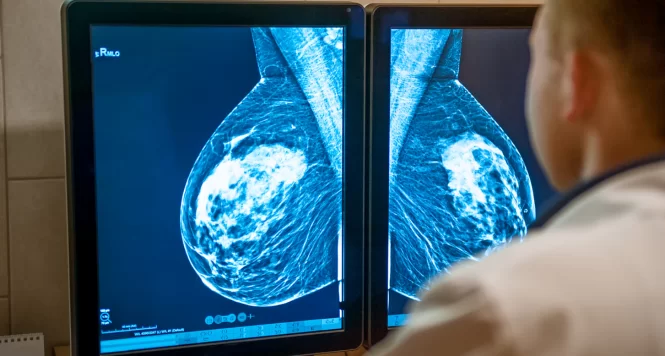

Apesar de ser essencial no combate ao câncer de mama, a mamografia ainda levanta debates sobre seus efeitos positivos e negativos. Entenda o que a ciência diz.

A mamografia é, sem dúvida, uma das principais ferramentas na luta contra o câncer de mama. Ao permitir a detecção precoce da doença, aumenta as chances de tratamento menos agressivo, melhora o prognóstico e salva vidas. No entanto, esse mesmo exame também gera questionamentos entre especialistas e pacientes, especialmente quando se fala em sobrediagnóstico e em impactos emocionais de resultados imprecisos.

Segundo estudos recentes da Sociedade Brasileira de Mastologia, a mamografia pode ser vista sob duas perspectivas: a de quem reconhece seu papel fundamental na redução da mortalidade e a de quem aponta os riscos de excesso de exames, ansiedade e até tratamentos desnecessários.